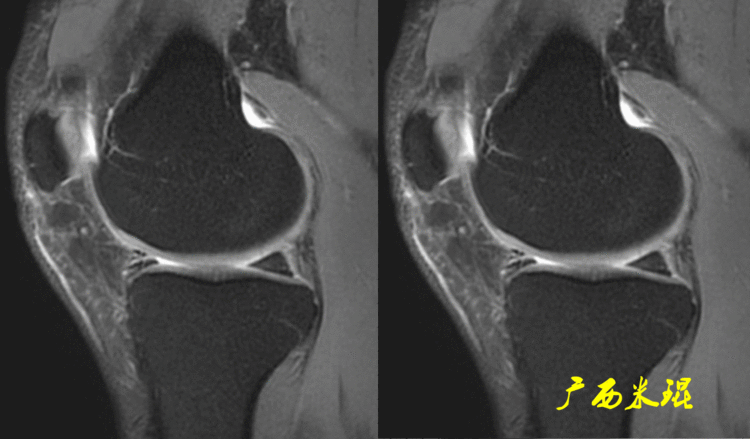

一、半月板损伤MR诊断的思路1、单纯就半月板改变诊断半月板损伤半月板信号(3级信号)及形态的异常是诊断半月板损伤最为直接的征象,当我们在阅片当中发现这些征象,一般情况下都能够确诊半月板损伤,下面这张MR,我们发现外侧半月板后角出现3级信号,所以能够确定其半月板损伤。

2、从发病机制诊断半月板损伤并不是每个病人都能够这么清晰的显示半月板的信号改变,同样这张MR,我们发现患者出现明显的对吻征,対吻征是诊断ACL损伤的重要体征,说明病人受伤的同时膝关节扭转严重,甚至出现轴移,这种情况下(损伤/发病机制)外侧半月板后根极其容易受伤,我们再认真的阅看其他截面,就很容易找到半月板损伤的佐证。